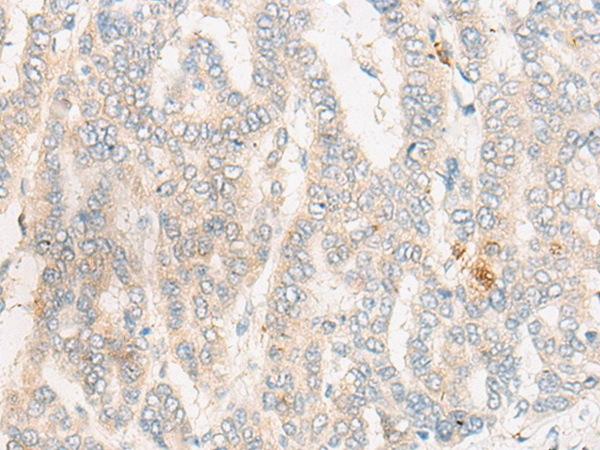

分类: 科研抗体货号: P06321别名: GY2; FKSG1; WDR14; WDVCF; DGCRK3应用: IHC反应种属: Human, Mouse